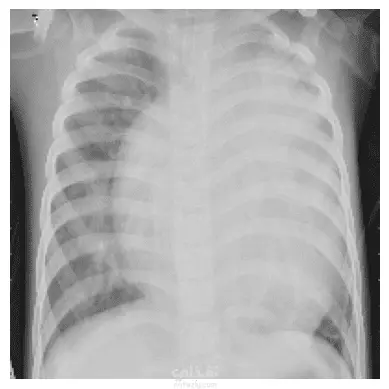

التعرف على ال (Pneumonia) -مرض رئوي- من خلال صور الاشعة التعرف على ال (Pneumonia) -مرض رئوي- من خلال صور الاشعة التعرف على ال (Pneumonia) -مرض رئوي- من خلال صور الاشعة التعرف على ال (Pneumonia) -مرض رئوي- من خلال صور الاشعة

في هذا المشروع قمت بتصميم وتدريب شبكة عصبية تلافيفية (CNN) مخصصة لاكتشاف الإصابة بالتهاب الرئة من صور الأشعة الصدرية (Chest X-Rays). بلغت دقة عاليّة (Precision تصل إلى 95٪) في تمييز الحالات الإيجابية بدقة من بين الصور المتاحة. خطوات المشروع تشمل: استيراد وتجهيز بيانات الصور (تأمين التوازن، تقسيم بيانات التدريب والاختبار). بناء بنية مخصصة لشبكة CNN، تشمل طبقات تلافيفية، تجميع (Pooling)، التطبيع (Batch Normalization) وطبقات تسلسلية نهائية. تدريب النموذج، ضبط المعاملات (hyperparameters) لتحسين الأداء. تقييم النموذج باستخدام مقاييس مثل Precision، Recall، Accuracy وغيرها. تحليل النتائج وإظهار الصور التي تم التصنيف فيها بدقة أو أخطأ النموذج لتوضيح نقاط القوة والضعف. الهدف العام للمشروع: تقديم نموذج قوي ودقيق يمكن استخدامه للمساعدة في التشخيص المبكر للحالات المحتملة من الالتهاب الرئوي، مما يسهم في تحسين السرعة والدقة في عملية الفحص الطبي.